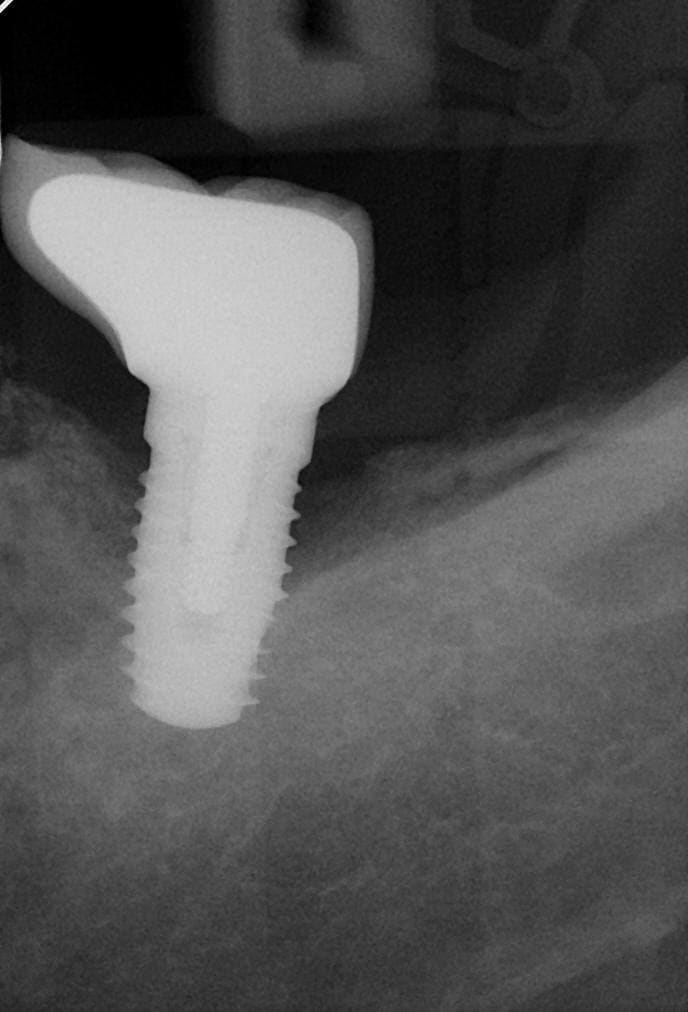

Cookie Consent byPrivacyPolicies.comIdentification implant - Eugenol

Identification implant

Oifhyzez1s4aybqbl40b - Eugenol

C est un global d inkone..

un inkone......je crois pas...

l'inkone a une spire qui se dédouble au col et là non....

http://osseosource.com/dental-implants/product_info.php?manufacturers_id=93&products_id=1912

moi j'aurais plutôt dit un Axiom...

http://osseosource.com/dental-implants/product_info.php?manufacturers_id=20&products_id=1942

Yep ça ressemble fort à un Axiom

oui axiom me semble t il